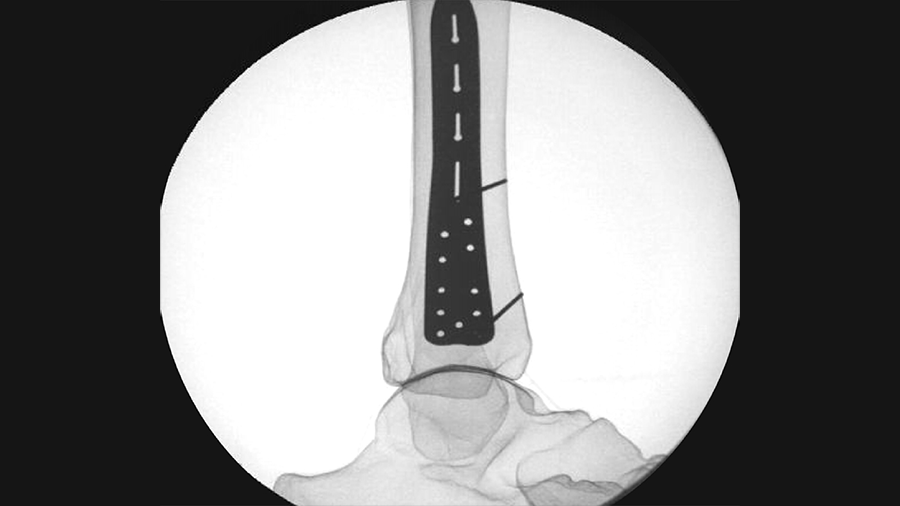

Once the DPS Hammertoe CCI is inserted into the bone and released from the Insertion Stick, the implant attempts to regain its original shape with converging legs thereby providing active continuous compression at the fusion site (Fig 4). The design with the four legs orthogonal to the bone axis and the active compression feature are beneficial for the distraction resistance (Fig 5).